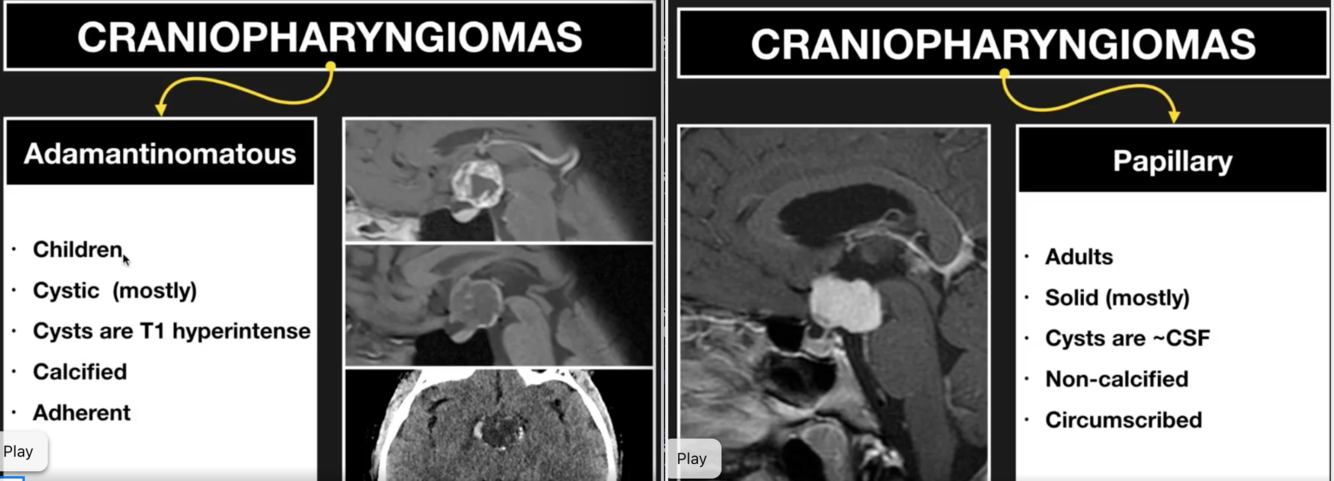

What is a Craniopharyngioma?